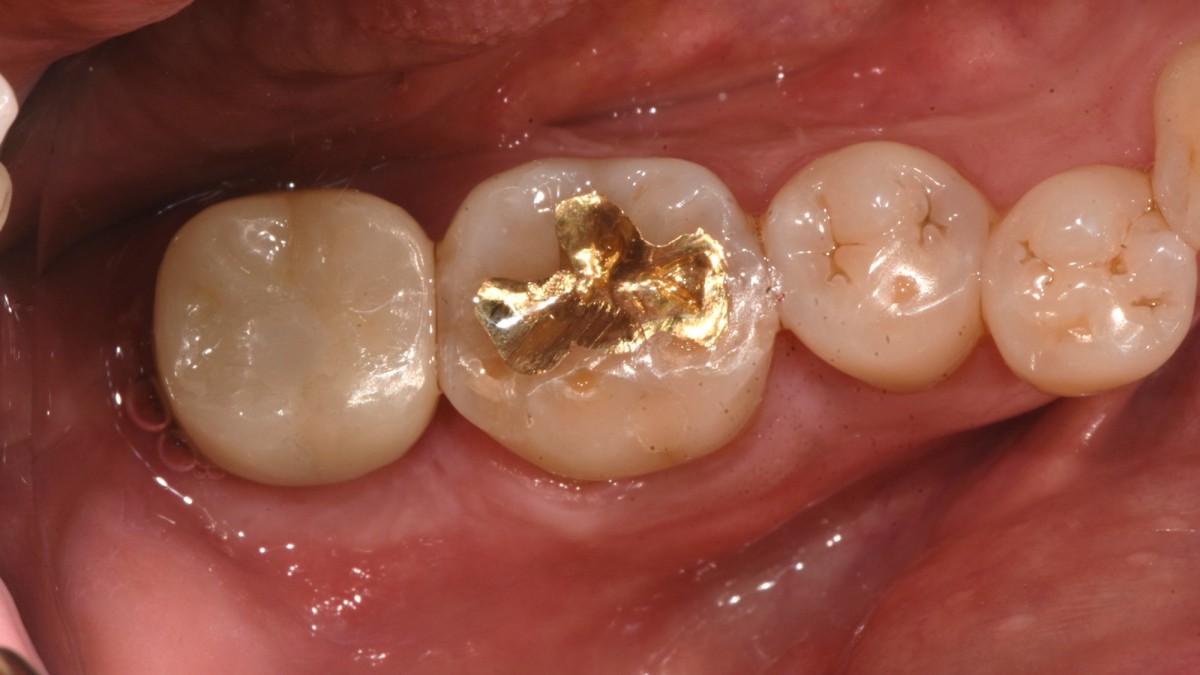

A 47-year-old male patient had a crown with an ill-fitting margin and crack-tooth syndrome in the lower 2nd molar. No systemic issue.